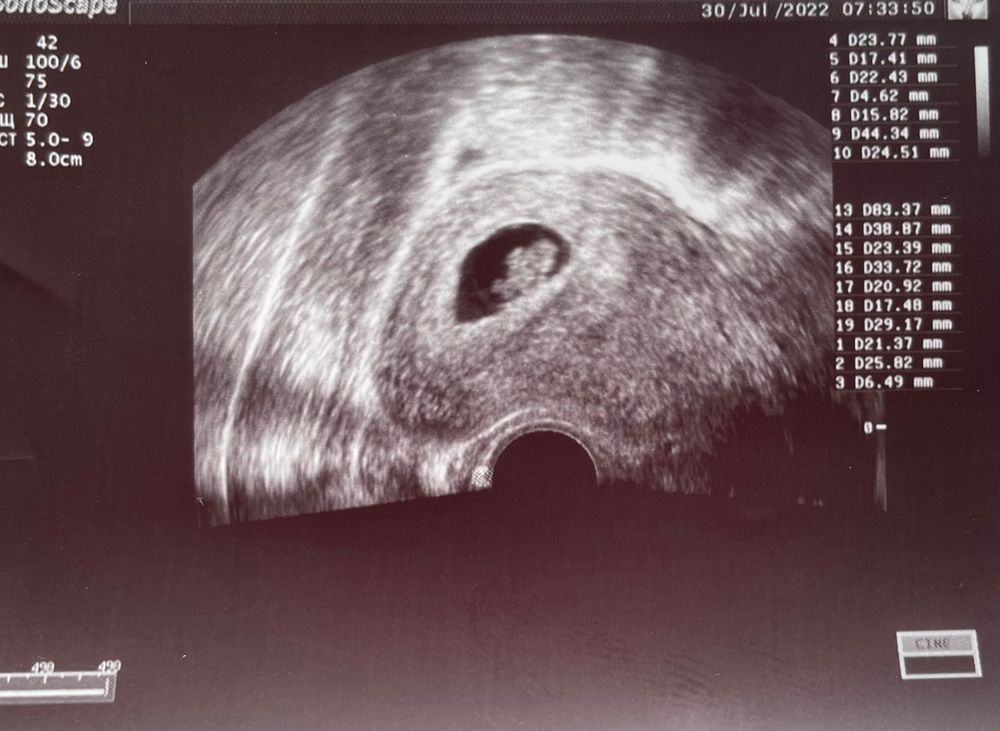

8 нед 3 дня - полёт нормальный ❤️

Странно так, у меня ктр 22 ПЯ 35 и срок написали 8 недель 4 дня 🤔 хотя по месячным 9,4 срок, сказали отстаём на недельку. 😒